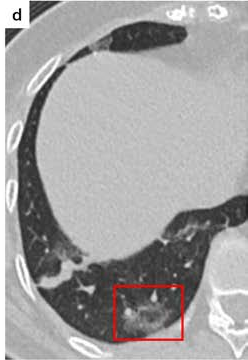

In a similar way, we consider classifying the test CT scans from the COVID-19 dataset by the DenseNet169 model and highlight the important regions considered for predictions. We present the original CT images and their localization maps in Figure 13. We can also see that our model is capable to detect the COVID-19 related regions as marked (small square in some images) by expert radiologists.

Figure 16 shows various CT scans where only one lung is visible. The CT scans are also extracted from the paper [58] and show different CT manifestations of COVID-19 pneumonia marked by red squares. The InceptionV3 model is capable to classify them correctly as COVID-19, although it is trained on CT scans where the entire lung is visible. Intriguingly, when applying Grad-CAM we can see that all regions of abnormalities are accurately localized. This also proves the potential of our model to detect COVID-19 abnormalities in CT images outside the dataset used for training.